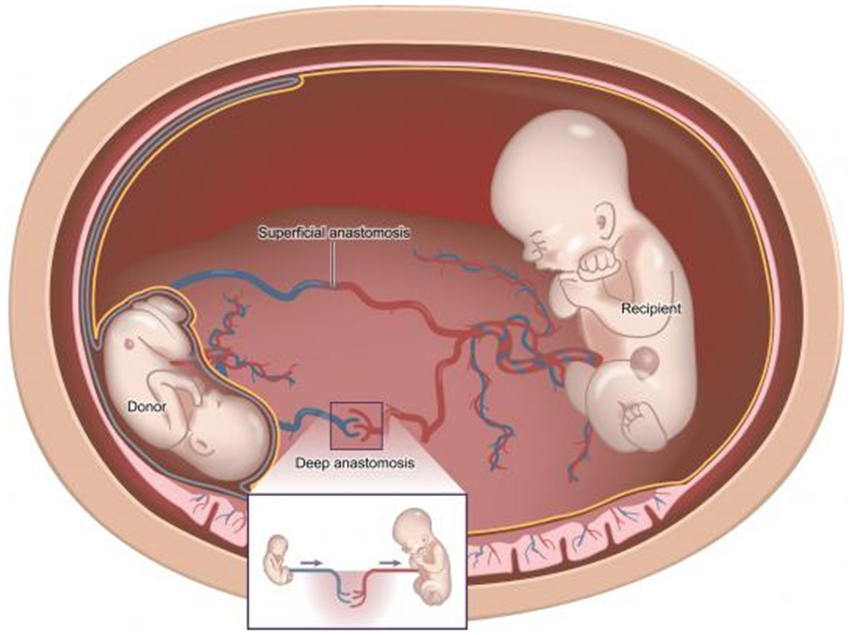

- இரட்டை-இரட்டை மாற்றுநோய்க்குறி (TTTS) பொதுவாக மோனோகோரியோனிக் இரட்டையர்களில் ஏற்படுகிறது. ஆனால் இதுமோனோகோரியானிக் மற்றும் டைகோரியானிக் மும்மடங்குகளிலும் நிகழ்கிறது.

ட்வின்டுட்வின் டிரான்ஸ்ஃபியூஷன் சிண்ட்ரோம் என்றால் என்ன?

ட்வின்-டு-ட்வின்டிரான்ஸ்ஃப்யூஷன் சிண்ட்ரோம் (டிடிடிஎஸ்) நஞ்சுக்கொடியை (மோனோகோரியானிக் இரட்டையர்கள்) பகிர்ந்து கொள்ளும் ஒரேமாதிரியான இரட்டையர்களை பாதிக்கலாம்.

இரண்டு இரட்டையர்களையும் இணைக்கும்நஞ்சுக்கொடி இரத்தநாளங்களில் ஏற்றத்தாழ்வுஏற்பட்டால் TTTS நிகழ்கிறது. இரட்டையர்களுக்கு இடையில்இரத்தம் சீராகப்பாயவில்லை என்றால், ஒருவர் அதிக இரத்தத்தைப்பெறுகிறார், இதுபெறுநர் இரட்டை என்று அழைக்கப்படுகிறது, மற்றொன்று குறைவான இரத்தத்தைப்பெறுகிறது (தானம்செய்யும்இரட்டையர்).

சமச்சீரற்ற இரத்தஓட்டம், தானம் செய்பவர்களைவிட கூடுதல்ஊட்டச்சத்துக்கள் மற்றும்திரவம் காரணமாக, பெறுநரின்இரட்டையர் பெரிதாகவளர்கிறது.

பெறுநர்இரட்டை எடுக்கும் கூடுதல்திரவம் இதயத்தில் ஒரு அழுத்தத்தை ஏற்படுத்தும்.உடல் அதிகசிறுநீரை உற்பத்திசெய்வதன் மூலம்திரவத்தை அகற்றமுயற்சிக்கும். இதன்விளைவாக, பெறுநரிடம் அம்னோடிக் திரவம் அதிகமாக இருக்கும், அதேசமயம் நன்கொடையாளரிடம் சிறிதளவு அல்லது எதுவும் இருக்காது.

பெறுநரின் இரட்டை மற்றும் கூடுதல் திரவம்கருப்பையின் (கருப்பை) சுவருக்கு எதிராக நன்கொடையாளர் இரட்டையை அழுத்தலாம்.இதுதாய்க்கு அசௌகரியத்தைஏற்படுத்தலாம் மற்றும் சுருக்கங்கள் கூட ஏற்படலாம்.

நஞ்சுக்கொடியைப்பகிர்ந்துகொள்ளும் பெரும்பாலான இரட்டையர்கள் சாதாரணமாக வளரும். பெரும்பாலான மோனோகோரியானிக் இரட்டையர்கள் TTTS ஐ உருவாக்கவில்லை. சிகிச்சையளிக்கப்படாவிட்டால் TTTS மிகவும் தீவிரமானது. இருப்பினும், சிகிச்சையானது குறிப்பிடத்தக்க சதவீத வழக்குகளில் வெற்றிகரமாக உள்ளது.

TTTS க்கானஸ்கேன் ஒவ்வொரு இரண்டுவாரங்களுக்கும் 16 வாரங்கள்முதல் 24 வாரங்கள் வரை நடைபெறும்.TTTS வளர்ச்சியடைவதற்கான அறிகுறிகள் இருந்தால், நோயாளி வாராந்திரஸ்கேன் செய்து மேலும்சிகிச்சைக்கு உட்படுத்தவேண்டும்.

கருமருத்துவநிபுணர் பலவிருப்பங்களை வழங்கமுடியும். ஒன்று அம்னோடிக்திரவத்தைஃபுல்லர்சாக்கில் (அம்னியோடிரைனேஜ்) வெளியேற்றுவது. இதுசமச்சீரற்றதன்மையை சரி செய்யவும் மற்றும் லேசான அல்லது மிதமான TTTS இல்கருப்பைக்குள்அ ழுத்தத்தைகுறைக்கவும் உதவும்.

TTTS இன்கடுமையான நிகழ்வுகளில், 26 வாரங்களுக்குமுன், மற்றொரு விருப்பம்உள்ளது. நஞ்சுக்கொடியில்உள்ள பாத்திரங்களை மூடுவதற்கு நிபுணர்லேசரைப்பயன்படுத்தலாம். இரண்டு இரட்டையர்களை இணைக்கும் அசாதாரணவாஸ்குலர் இணைப்புகளை அழிக்கலேசர்கற்றை பயன்படுத்தப்படுகிறது. இதுஒ ருஃபெடல்மெடிசின் நிபுணரால் மயக்கமருந்தின் கீழ்செய்யப்படுகிறது. செயல்முறைசுமார் 30 முதல் 60 நிமிடங்கள் ஆகும். தாயின் வயிற்றில் ஒருநிமிடகீறல்மூலம் அம்னோடிக் குழிக்குள் ஒரு சிறிய தொலைநோக்கிசெருகப்படுகிறது. பார்க்கப்பட்ட அசாதாரண பாத்திரங்கள் பின்னர் வெப்பத்தைப்பயன்படுத்தி மூடப்படும்.

இது இரட்டையர்களுக்கு இடையேயான இரத்த சமநிலையின்மையை நிறுத்தும்.